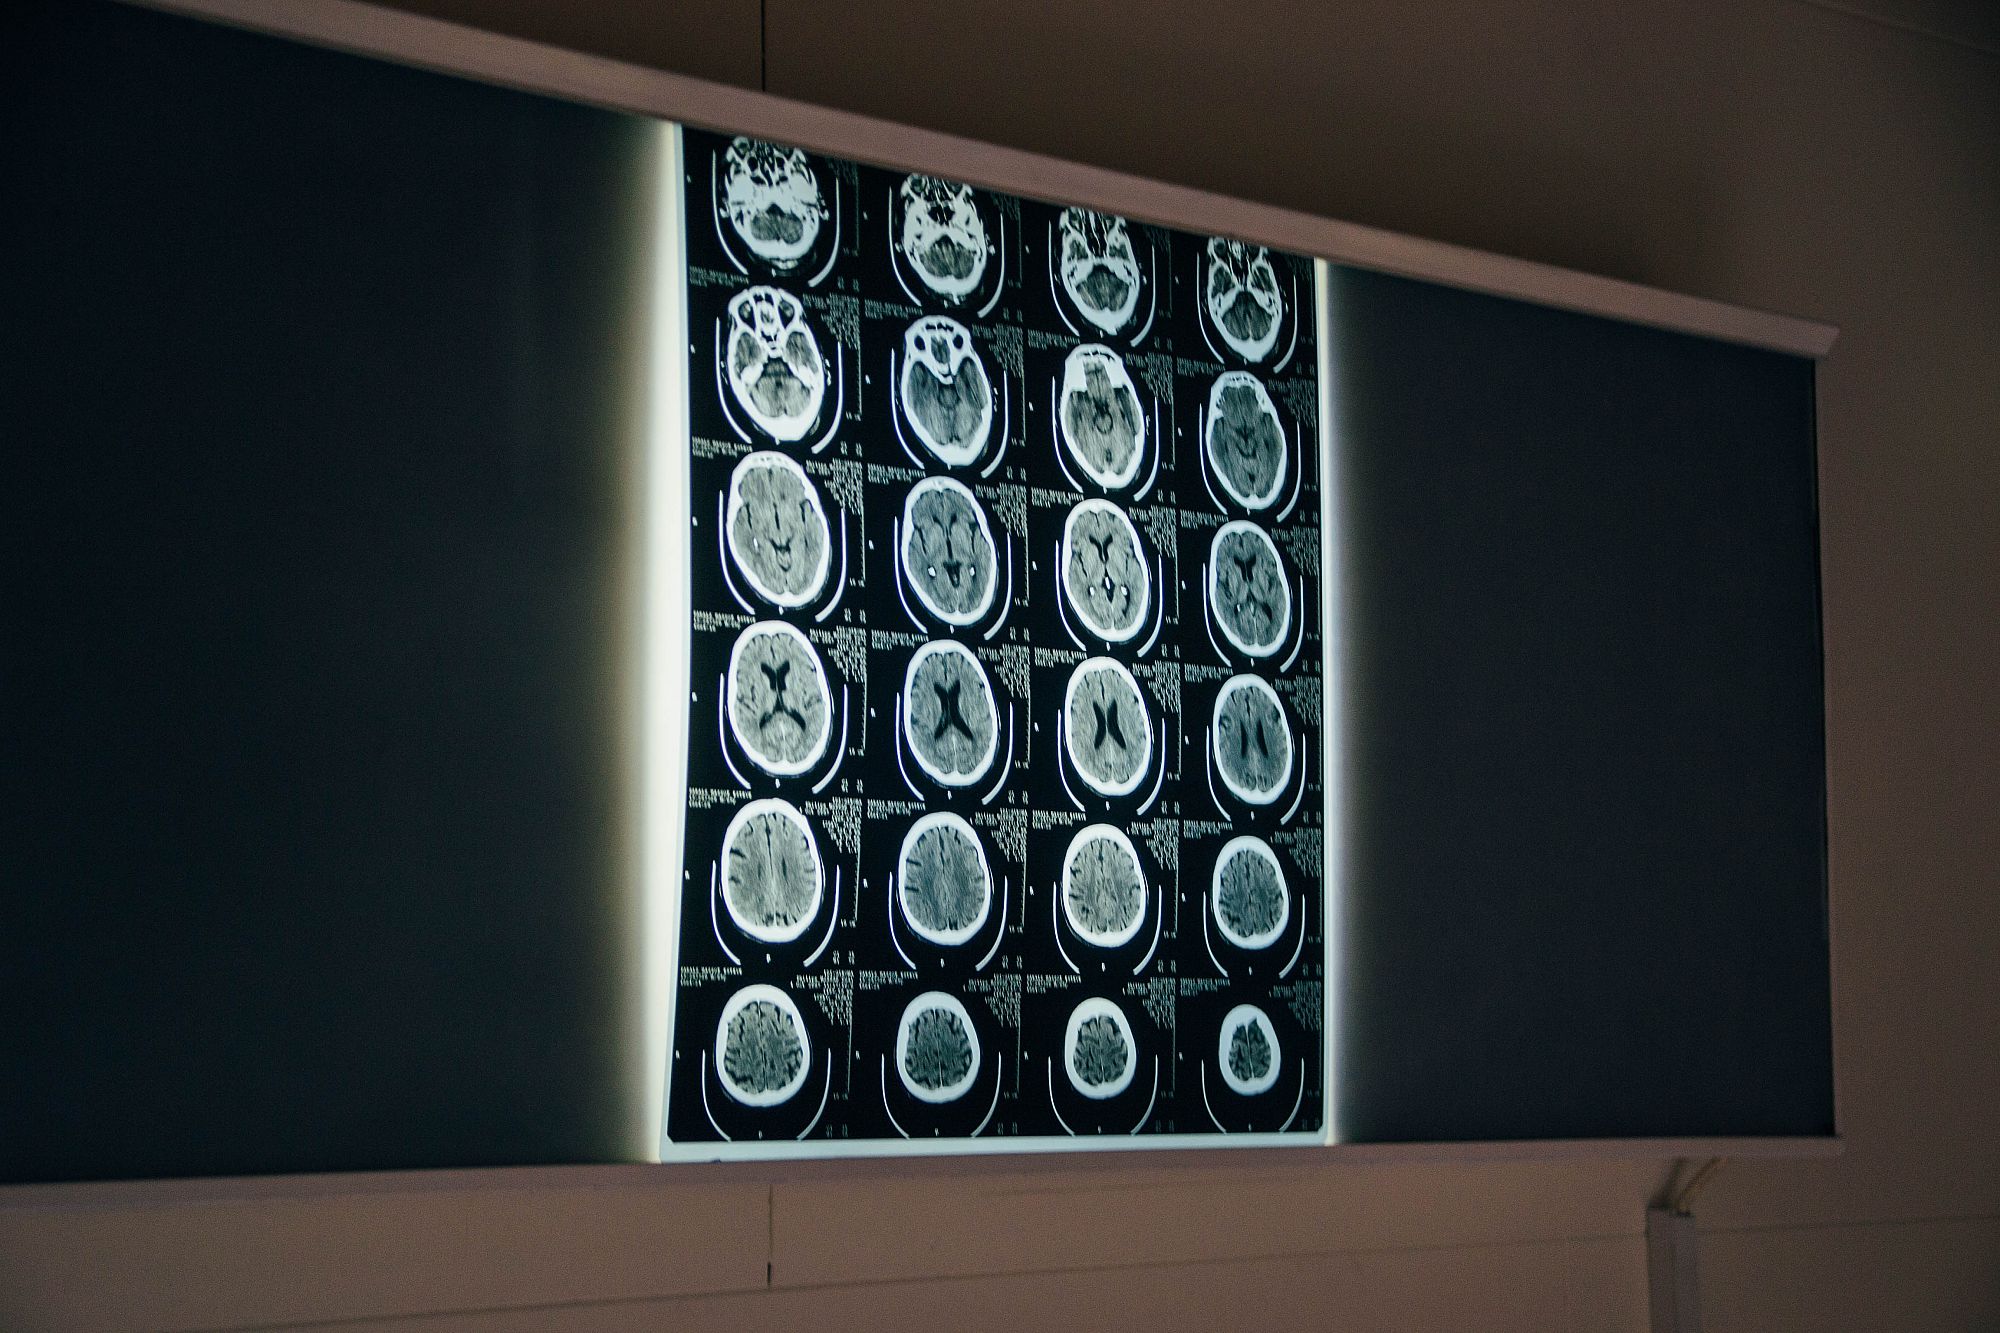

It is a project of making of short films that revolves around the concept of the internal duality of the people. The synopsis of which seeks to narrate a moral conflict of two doctors, who have to operate a corrupt politician, who has cut in health and predictably continue to do so.